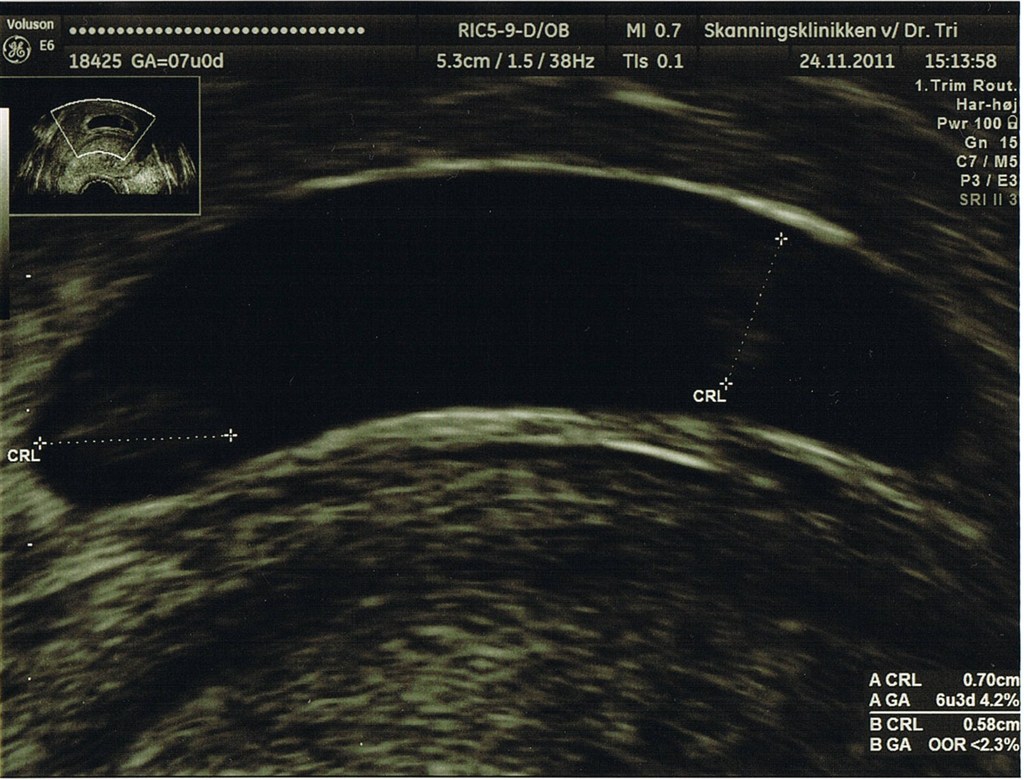

Er det tveæggende eller enæggende?